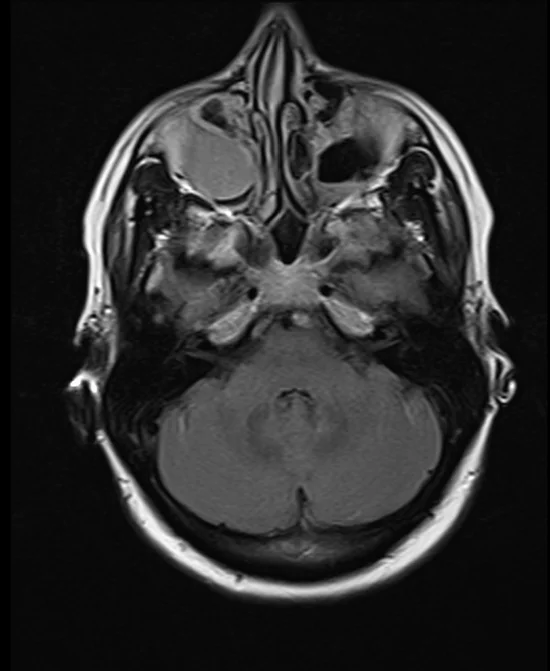

brain mri t2 flair axial images